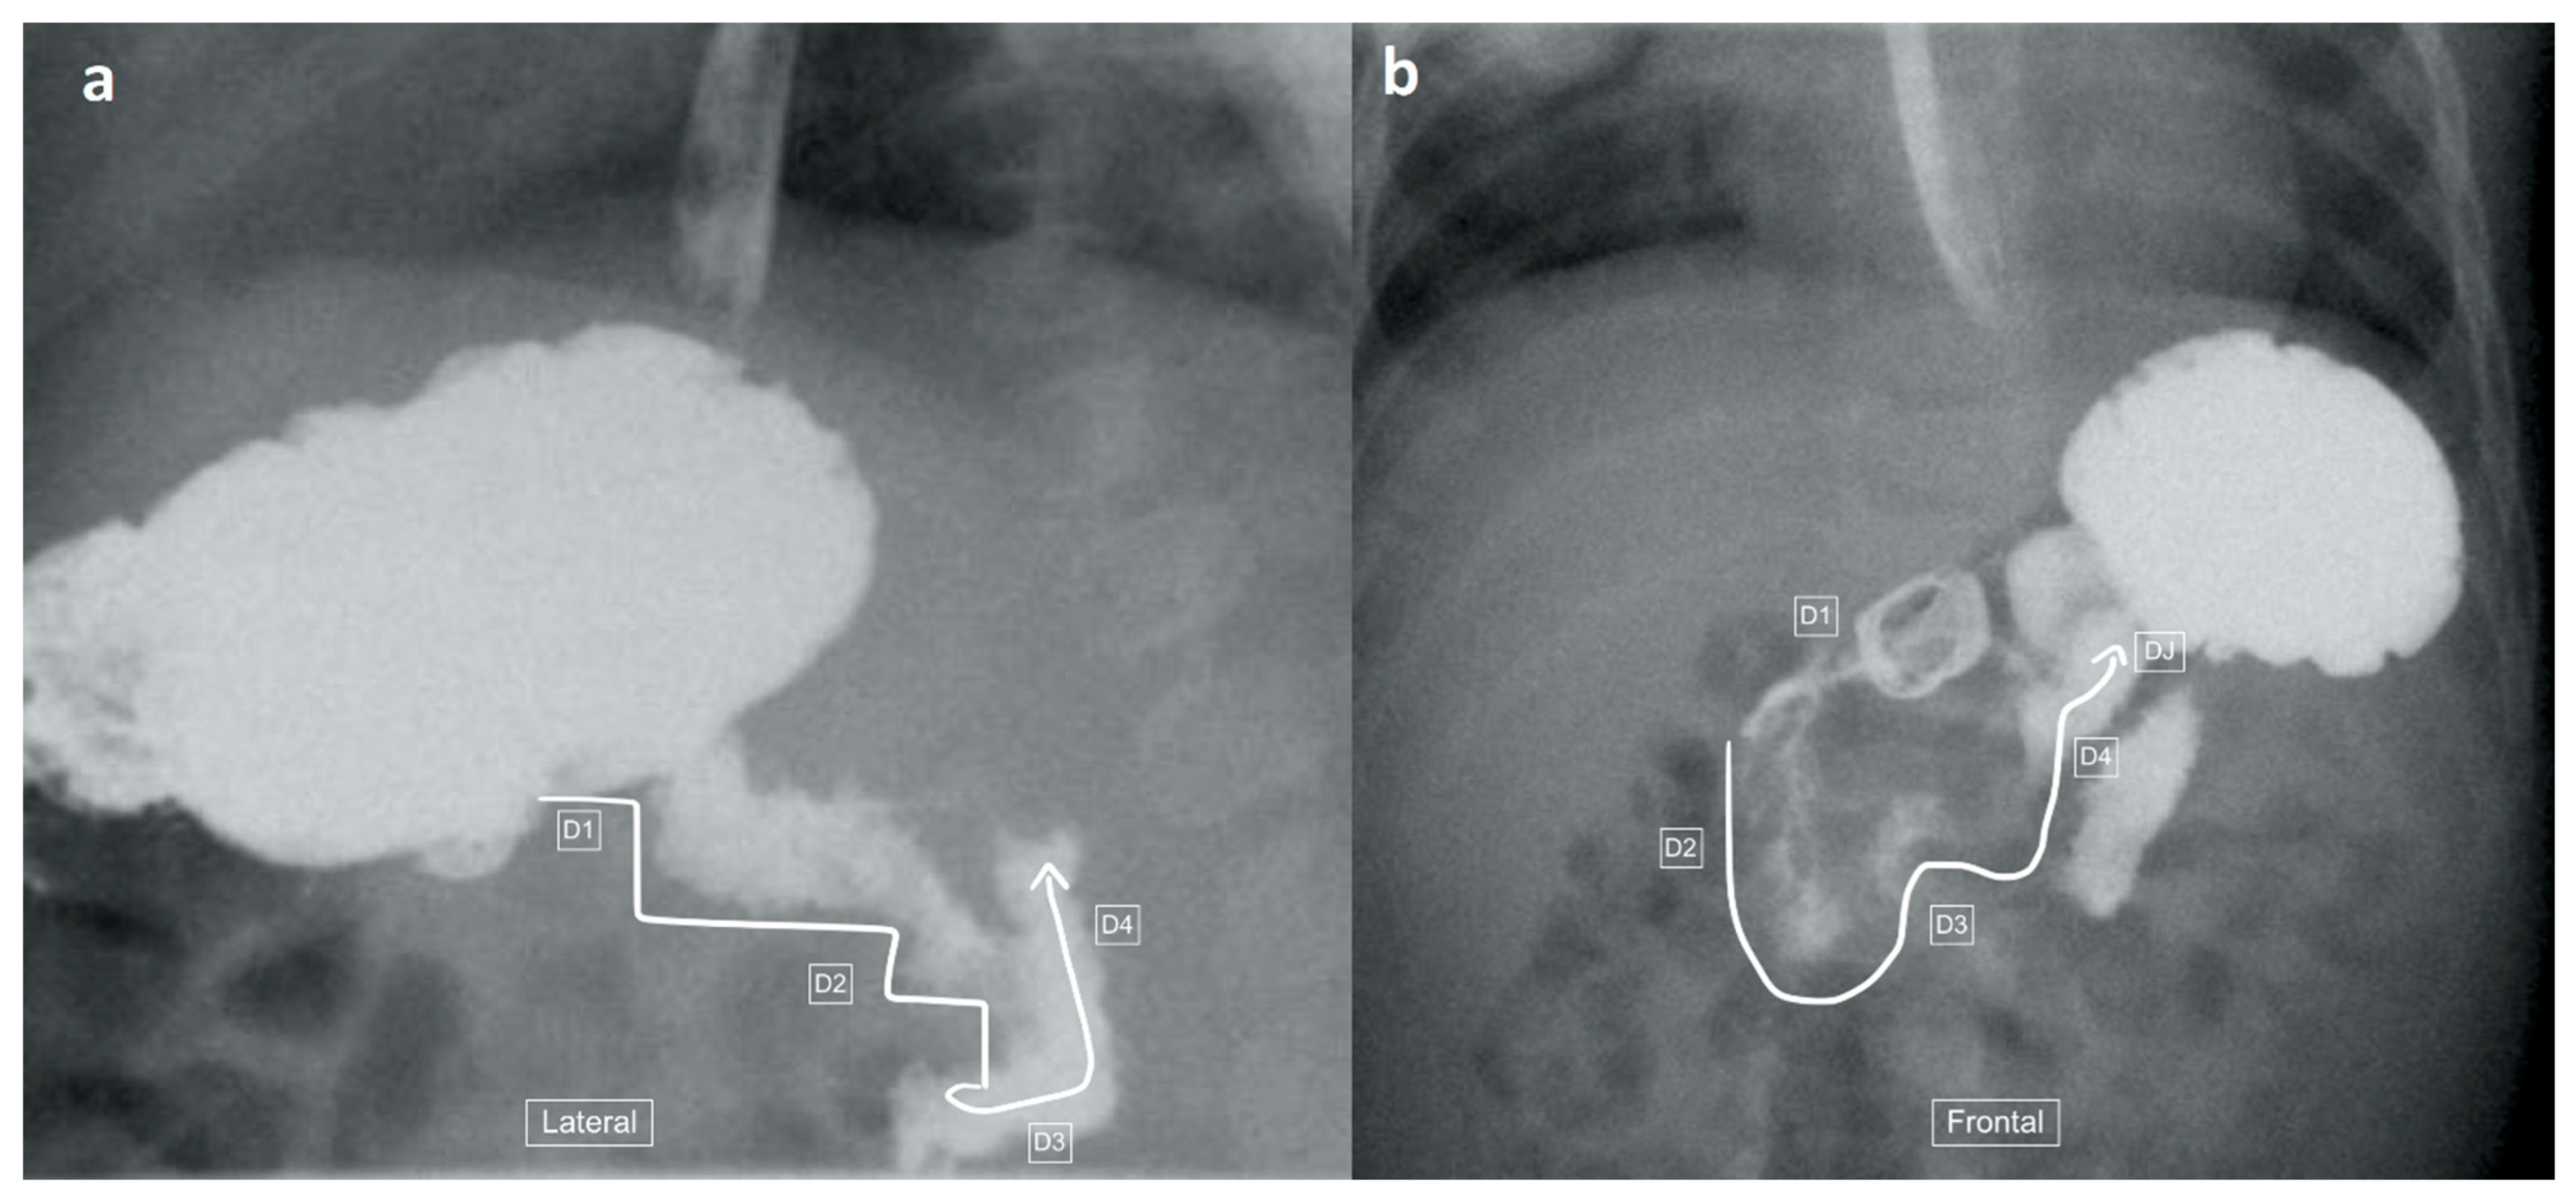

Figure 1.

(a) early and (b) later view: Sequential lateral views from an upper gastrointestinal tract study (UGIS) in an 8-year-old boy demonstrating the normal configuration of the duodenum which courses posteriorly (retroperitoneal) from the antrum (D1), descends posteriorly (D2), remains posterior at its most inferior portion (D3), ascends posteriorly again through (D4) and only then courses anteriorly from the duodeno-jejunal (DJ) flexure at the same height as the antrum and D1.